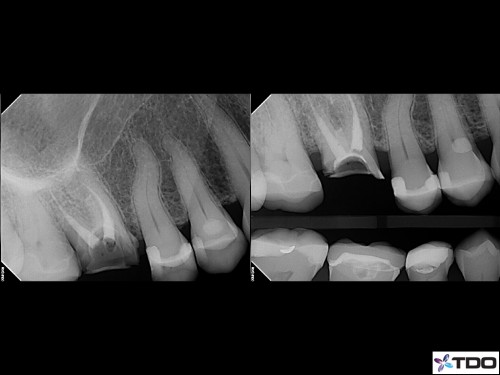

65 year-old female in good health. Root canal treatment was completed by my predecessor 15 years ago. She lost the post/crown two weeks ago. Tooth is asymptomatic. Referring doc asked if I would “do one of your magic cores so we can hold onto this tooth for a little bit longer.” No problem.

[post-views]